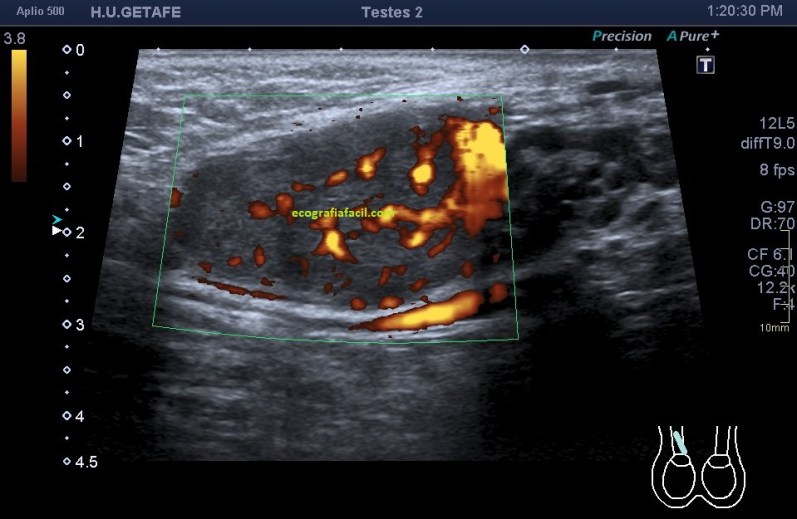

Una vez que tuve controlado el aspecto normal de músculo en la misma localización donde la paciente tenía el bulto, me dirigí a la región del bultoma y estudié la lesión, descrita con anterioridad, siguiendo el protocolo de actuación en caso de neoformaciones, control, medidas, doppler color y power y finalmente comparativa.

El estudio doppler arroja el hallazgo de un vaso importante que está alcanzando y nutriendo la región afectada. Puedes observar como es un vaso de alto flujo y de buen tamaño. No pude demostrar vascularización perimetral de la lesión.